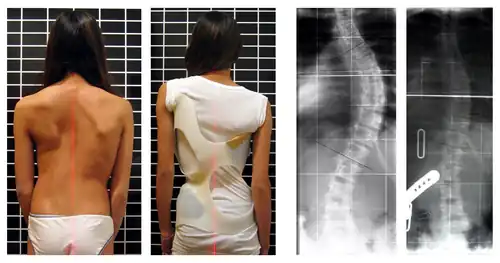

| Radiografia em que se observa deformação lateral da coluna causada por escoliose | |